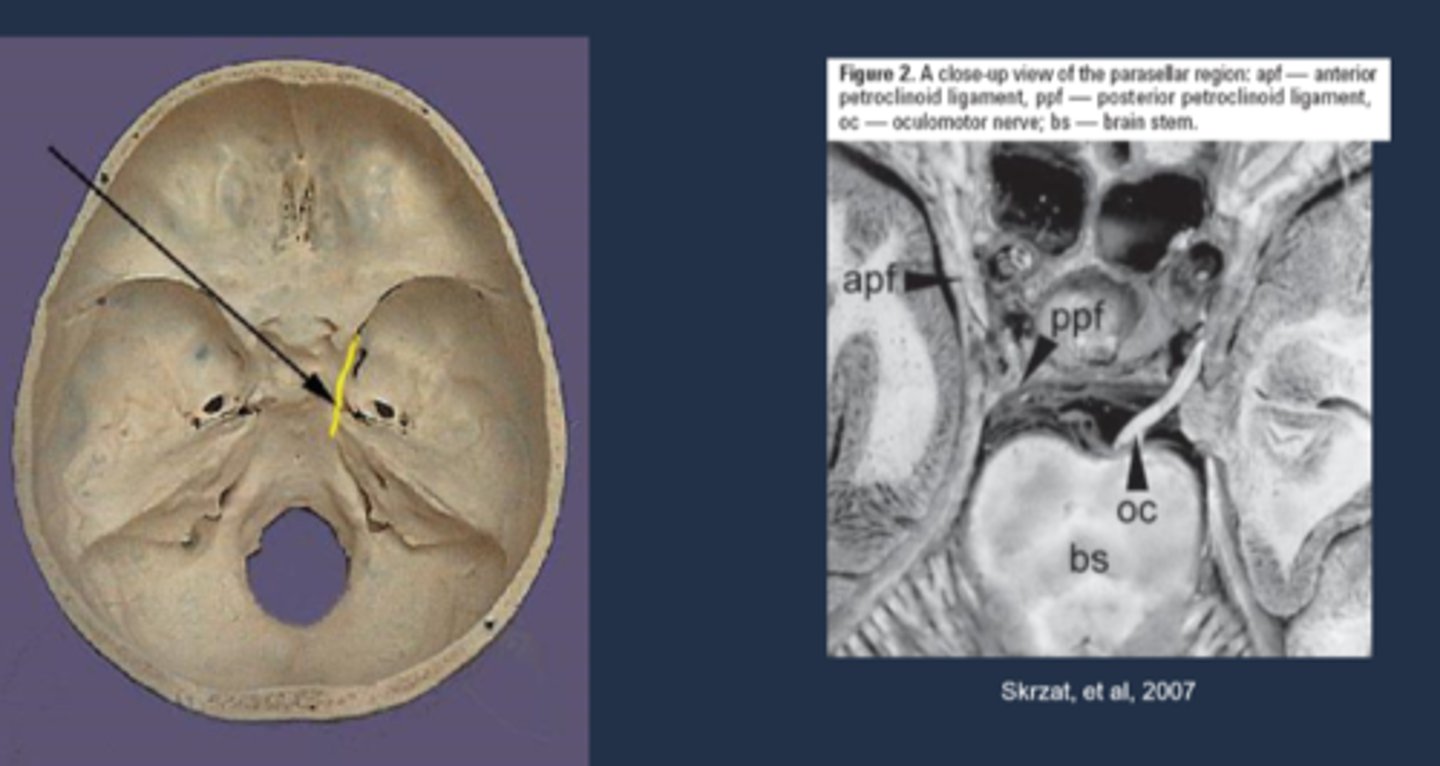

Where is the Uncal region, affected in Uncal syndrome?

uncas of parahippocampal gyrus (inferior area of temporal lobe) = lateral to the brainstem = lateral to CN III in brainstem

Explain how the Uncal region can affect CN III in Uncal syndrome.

CN III leaves brainstem = pupillomotor fibers move dorsomedially = uncus herniates = compresses CN III dorsomedially against petroclinoid ligament and dorsum sellae = pupil is blown